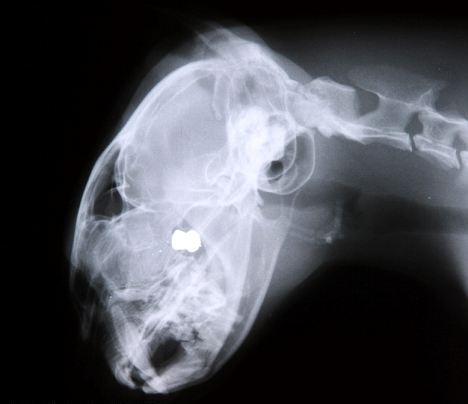

Το ανήμπορο γατάκι μπήκε τρέχοντας στο σπίτι της ιδιοκτήτριάς του Helen Connelly, ενώ από τη μουσούδα του έσταζε αίμα. Η 42χρονη Connelly από το Uddingston του νότιου Lankarshire, το άρπαξε και έτρεξε στον κτηνίατρο, ο οποίος αφού έκανε ακτινογραφία στη γάτα είδε ότι το βλήμα είχε καρφωθεί στο εσωτερικό του κρανίου της.

Εξαιτίας του σημείου που σφηνώθηκε οι κτηνίατροι δεν μπορούν να το αφαιρέσουν, καθώς η επέμβαση θα μπορούσε να προκαλέσει βλάβη στον εγκέφαλο της Cookie ενώ θα μπορούσε να αποβεί μοιραία.